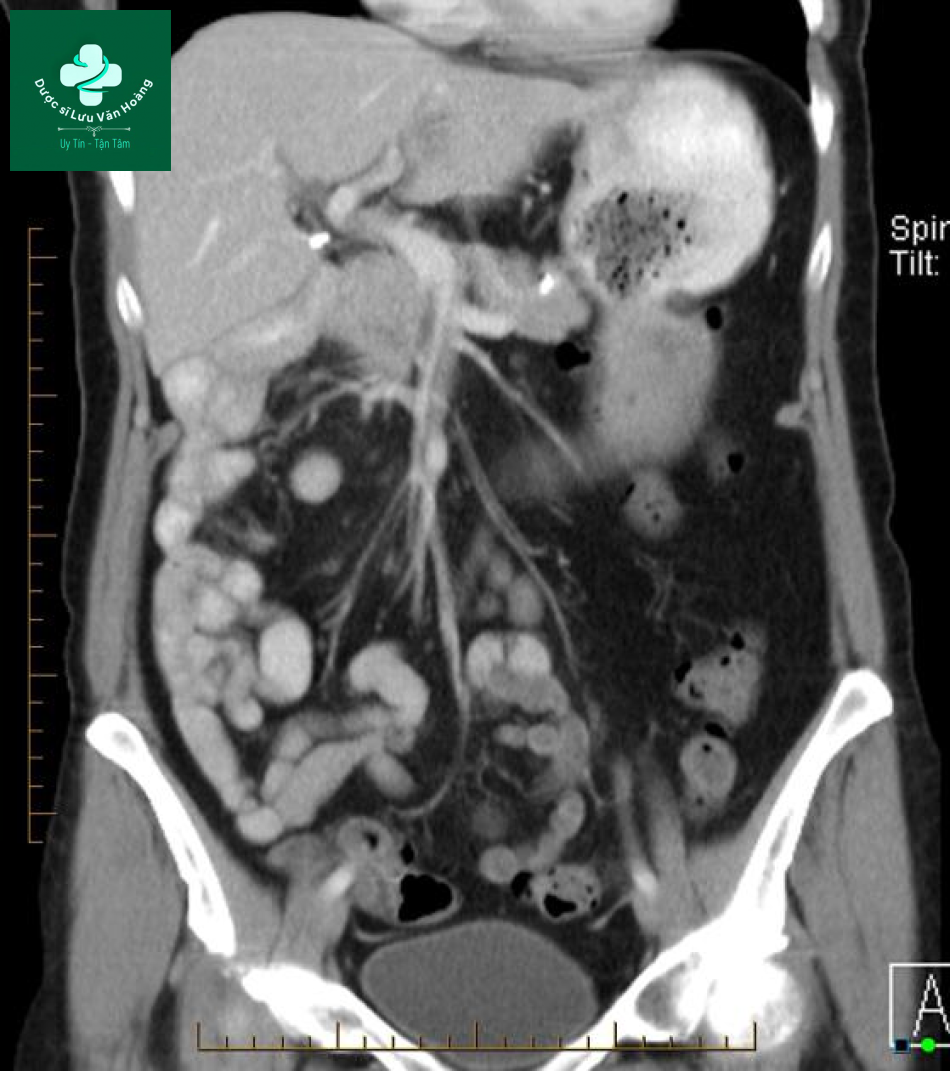

Bệnh nhân nữ, 65 tuổi, biểu hiện khó chịu vùng bụng và chướng 2 tháng nay.

Hình ảnh CT cho thấy các quai ruột non chủ yếu nằm bên phải, đại tràng nằm bên trái và có sự đảo ngược vị trí của SMA va SMV.